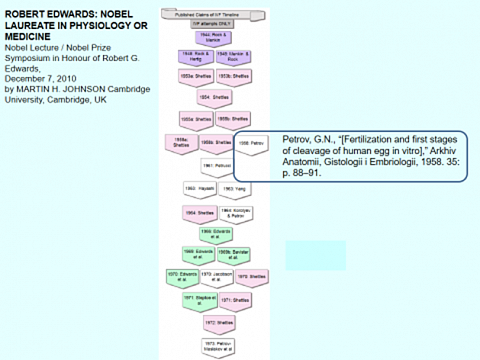

В 2010 году в Нобелевской лекции Мартина Джонсона, посвященной присуждению Роберту Эдварсу Нобелевской премии, упомянул имя Г.Н.Петрова среди ученых и врачей, чьи исследования обеспечилиразработку и внедрение экстракорпорального оплодотворения в практику лечения бесплодия.